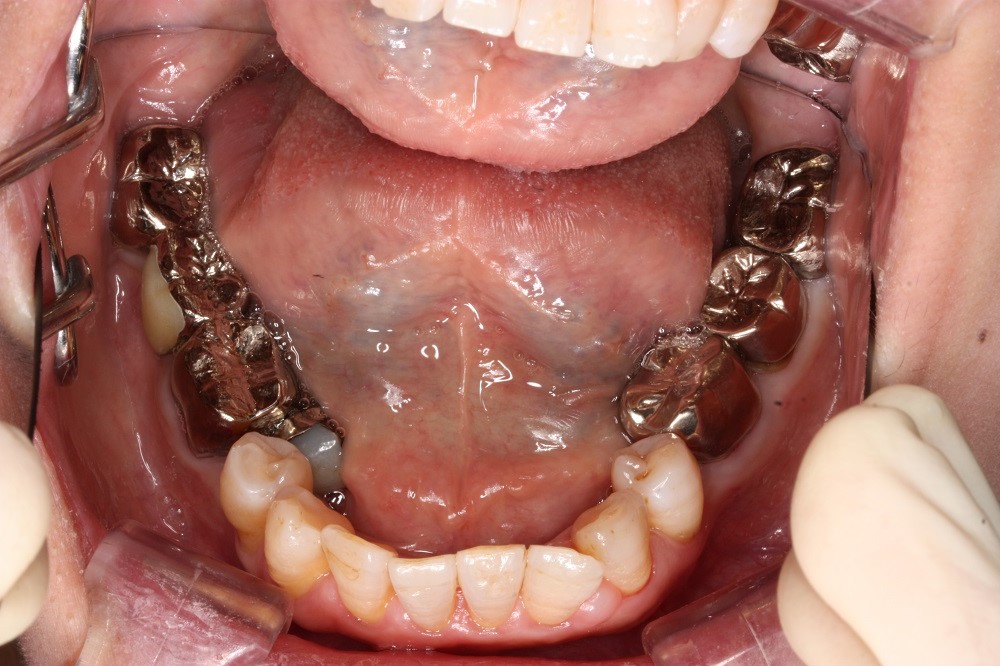

矯正治療後

40代女性の患者様です。

反対咬合が気になり来院されました。

ずっと気になっており、小学生の頃に一度矯正治療をしたということです。

分析の結果歯をぬく必要はなく、

歯のやすり掛けにより歯をやせさせる処置と

歯並びの横幅の拡大や歯の傾きを改善することによって

反対咬合と叢生を治療しました。

目立たないように治療したいと希望され通常の針金ではなく

ホワイトワイヤーを使用して治療を行いました。